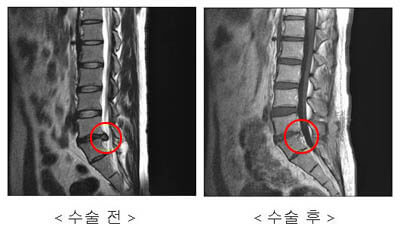

추간판 탈출증이라 불리는 허리디스크 증상은 크게 3단계로 나눌 수 있어요. 1단계는 내부 섬유륜이 파열하여 수핵이 빵빵한 상태, 2단계는 섬유륜 전체가 파열되어 수핵이 탈출하는 단계, 3단계는 완전히 탈출해 버린 단계입니다.

단계마다 느끼는 증상들이 조금씩 다른데요. 디스크의 보호막이 약간 찢어졌고 디스크가 약간 튀어 주변의 신경 뿌리에 닿으면 염증성의 통증이 발생하기 시작하면서 점점 증상이 심해지면 디스크의 파열은 골수를 이루고 있는 핵이 튀어나오면서 신경에 대한 물리적 압박을 가하고 참을 수 없는 아픔을 유발하게 돼요.